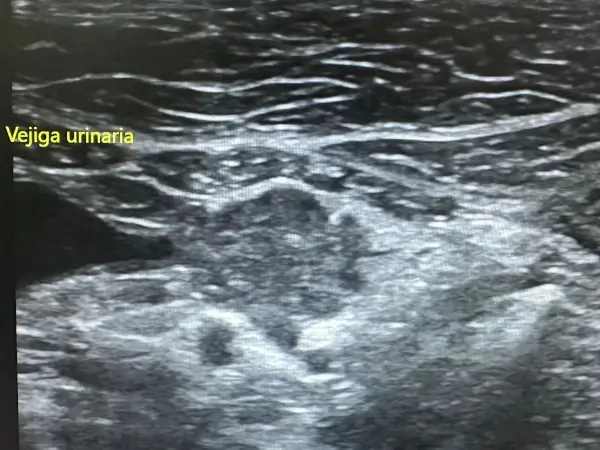

Ecografía abdominal y cardíaca: La ecografía es una técnica no invasiva que permite visualizar órganos internos en tiempo real, evaluando su estructura, tamaño y vascularización. A diferencia de la radiografía, no utiliza radiación y proporciona información sobre la arquitectura interna de los órganos.

Nuestro ecógrafo de alta gama con tecnología doppler color permite:

- Valoración de la vejiga y detección de cálculos urinarios

Análisis de orina: El examen del sedimento urinario es fundamental en medicina felina. Detectamos cristales que pueden formar cálculos, bacterias indicativas de infección, proteína que sugiere daño renal o glomerular, y células que orientan sobre patología del tracto urinario.